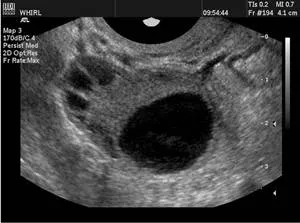

卵泡监测有以下几种方法:1)月经周期推算法;2)基础体温(BBT)测量法;3)排卵试纸检测法;4)宫颈粘液观察法;5)经阴道超声监测排卵。目前,B超是广泛、全面地监测排卵情况的方法。在B超下可以动态地测量卵泡的发育成长和大小,观察卵泡的排卵,观测子宫内膜的厚度和形态,非常精确、方便、无创伤。

●当卵泡>15mm时:每天或隔天监测。

●当卵泡>18mm时:为成熟卵泡,此时可根据医生的建议,合理安排诱导卵泡排出,此时同房怀孕就能事半功倍。

监测排卵应该同时监测内膜厚度,可以了解内膜与卵巢同步性及内膜状态。最后,由医生根据卵泡的大小及排卵时间指导同房的时间。